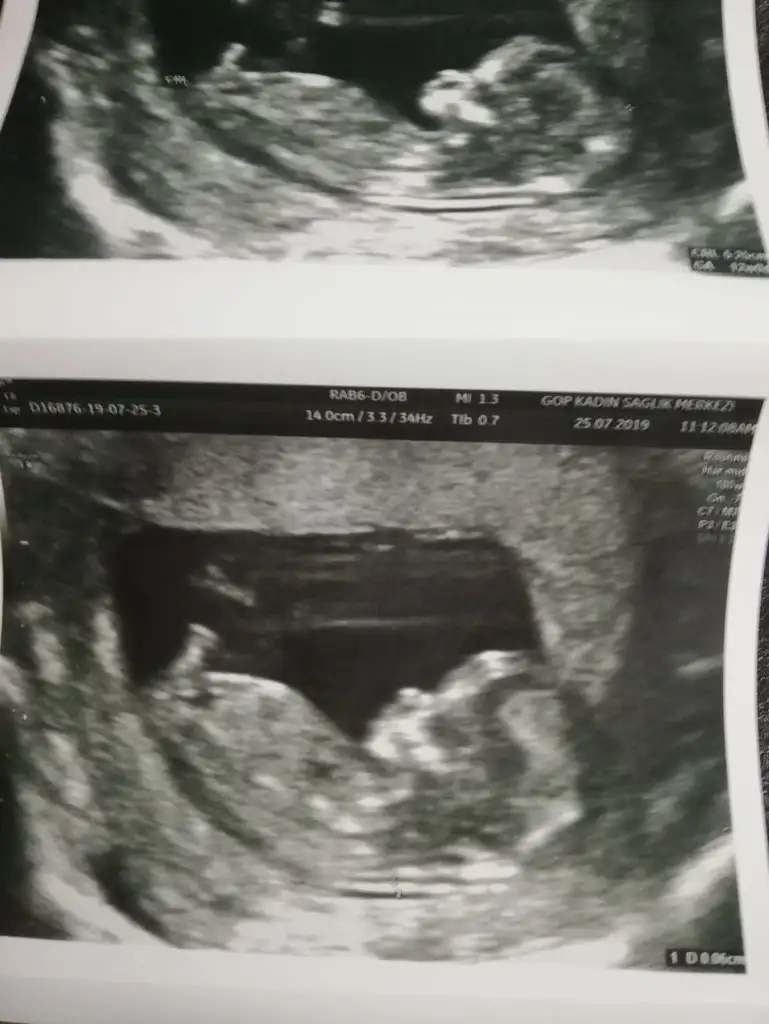

2li test için gittik ense ölçüümü gayet iyi dedi doktor 0,6mm boyu 5,25 cm tam 12+0 çıktı :)

burnu cok güzel ya fınfık burun :D

burnu cok güzel ya fınfık burun :KK70: